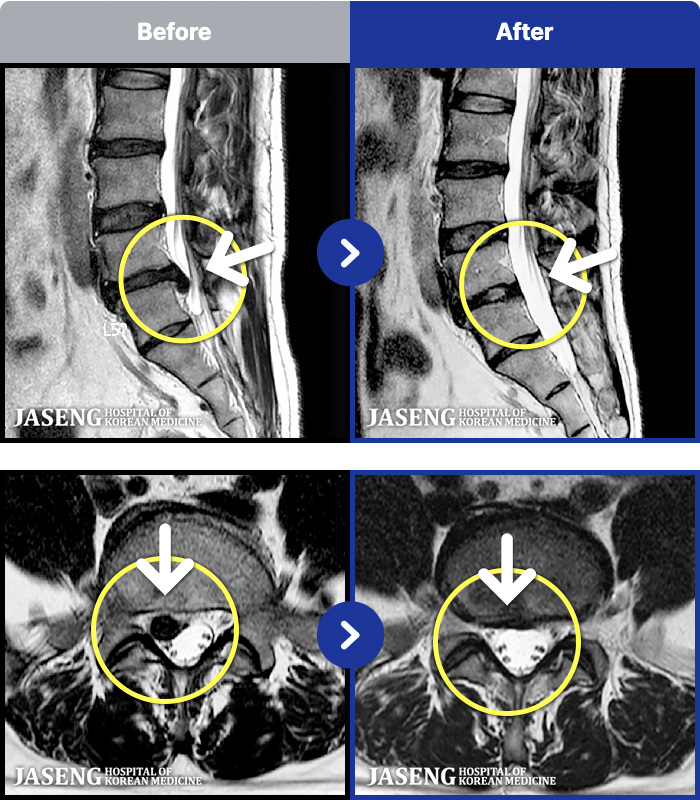

ȯںп Ǹ ǿ ԿǾ, ο ġ ۿ Ƿ ġḦ Ͻñ ٶϴ.